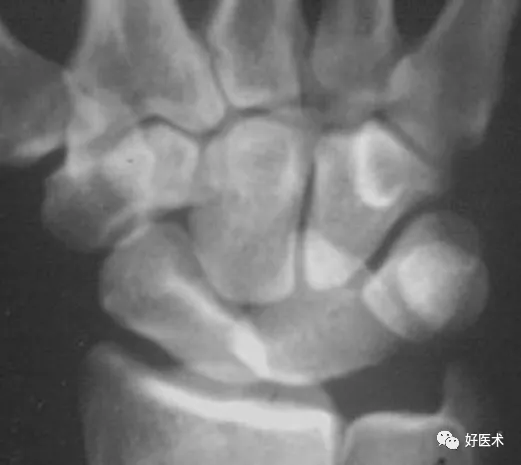

上圖顯示月骨和頭狀骨、鉤骨、三角骨異常重疊,而舟骨與其也不平行,橈月關節間隙異常增寬,其它腕骨間隙平行而勻稱。此為單純月骨脫位。